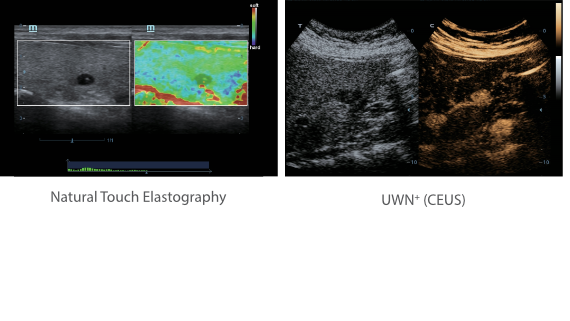

Based on the deep insights of customer needs, the DC-60 ECHO with X-Insight is designed to deliver high efficiency with precision imaging, which is empowered by eXpress Clarity, eXceptional Intelligence and eXceeding Experience.